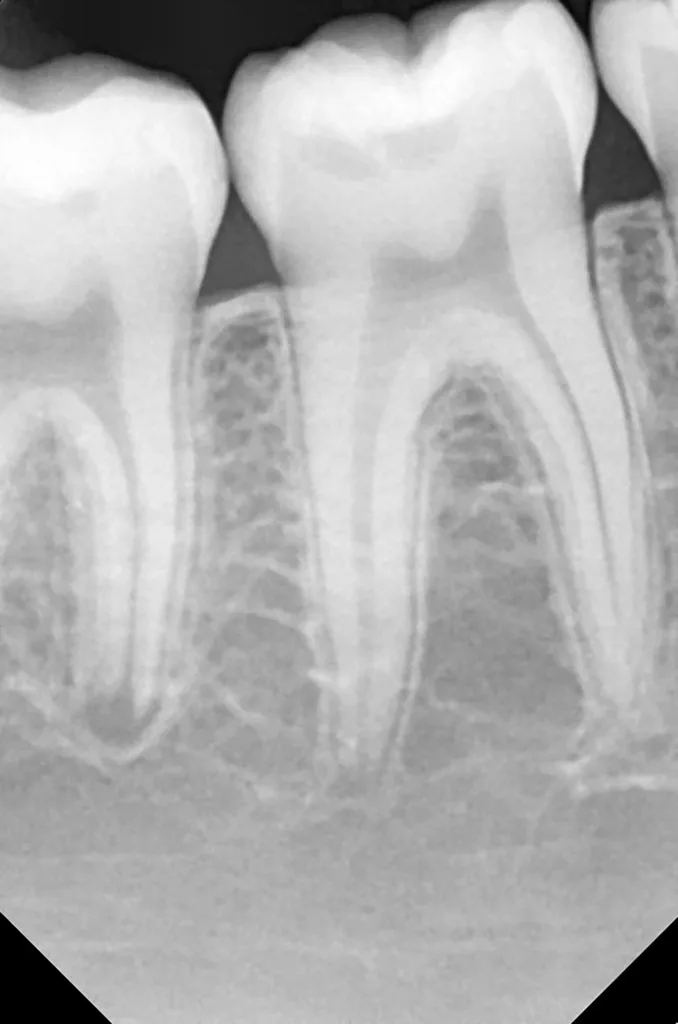

Bei routinemäßigen Röntgenkontrollen ergeben sich manchmal Zufallsbefunde unklarer Genese. So stellt sich beispielsweise bei der Betrachtung der Abbildung 1 die Frage, wie sich ein Zahnhartsubstanzdefekt so schnell entwickeln konnte. Ein weiteres Röntgenbild (Abb. 2), das vor dem Zahndurchbruch aufgenommen wurde, zeigt jedoch, dass es sich in diesem Fall nicht um Karies, sondern um die sogenannte präeruptive intrakoronale Resorption (PEIR) handelt. Für diesen Befund finden sich in der Fachliteratur auch noch andere Bezeichnungen wie „idiopathic external resorption of unerupted permanent teeth“ [1], „intra-follicular caries“ [2], „radiolucent lesions resembling caries“ [3], „occult caries“ [ 4] oder „pre-eruptive caries“ [5].

V. Slabkovskyi, O. LiutikovJahr vor dem Durchbruch des Zahnes 36.

Das fünfjährige Mädchen stellte sich 2017 zur jährlichen Routinekontrolle vor. Im Rahmen der Untersuchung wurden Röntgenaufnahmen der Milchmolaren gemacht (Abb. 2). Der klinische und radiologische Befund der vor uns früher gelegten Kompositfüllungen war gut, es wurde allerdings eine PEIR an den noch nicht durchgebrochenen ersten bleibenden Molaren festgestellt (Abb. 2). Den Eltern wurde empfohlen, sich unverzüglich bei Beginn des Durchbruchs der ersten Molaren erneut zur Behandlung vorzustellen. Ein Jahr später erschien die junge Patientin schmerzfrei zur Kontrolle. Der Zahn 36 war noch teilweise mit Gingiva bedeckt. Auf einer neuen Röntgenaufnahme (Abb. 1) wurde die PEIR-Läsion mit unveränderter Größe in pulpanahen Bereichen bestätigt (Grad 3 der Läsion nach Seow). Der Zahnschmelz sah intakt aus, es konnte kein pathologischer periapikaler Befund bei den noch nicht ausgewachsenen Zahnwurzeln festgestellt werden. Daraufhin wurden die verschiedenen Behandlungsmöglichkeiten von Fissurenversiegelung bis Vitalerhaltung der Zahnpulpa mit den Eltern des Kindes besprochen.